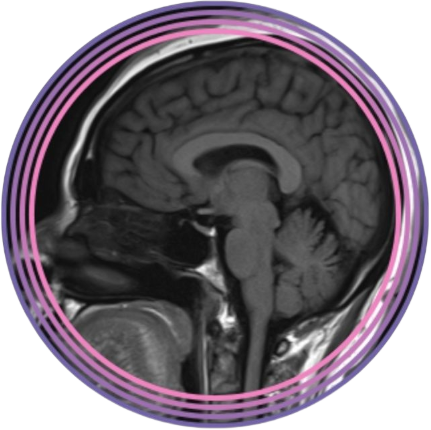

El diagnóstico por imagen del sistema nervioso central es una disciplina en constante evolución y de vital importancia para la práctica clínica. Por lo cual el conocimiento de una amplia variedad de patologías, desde tumores hasta accidentes cerebrovasculares, traumatismos craneoencefálicos y enfermedades neurodegenerativas, nos brinda habilidades para nuestra actividad laboral diaria.

La neuroimagen, como herramienta diagnóstica y de investigación, ha revolucionado nuestra comprensión del cerebro humano. Su aplicación en la práctica clínica ha permitido un diagnóstico más preciso y temprano de una amplia gama de enfermedades neurológicas, mejorando significativamente la atención al paciente.

Por otro lado, la evolución de las tecnologías de neuroimagen (RM, TC, PET, IA) ha ampliado considerablemente sus aplicaciones clínicas y de investigación. Así como también, la demanda de profesionales capacitados en neuroimagen ha aumentado considerablemente y que posean una formación sólida en los principios físicos, la anatomía, la fisiología y la patología del sistema nervioso central.